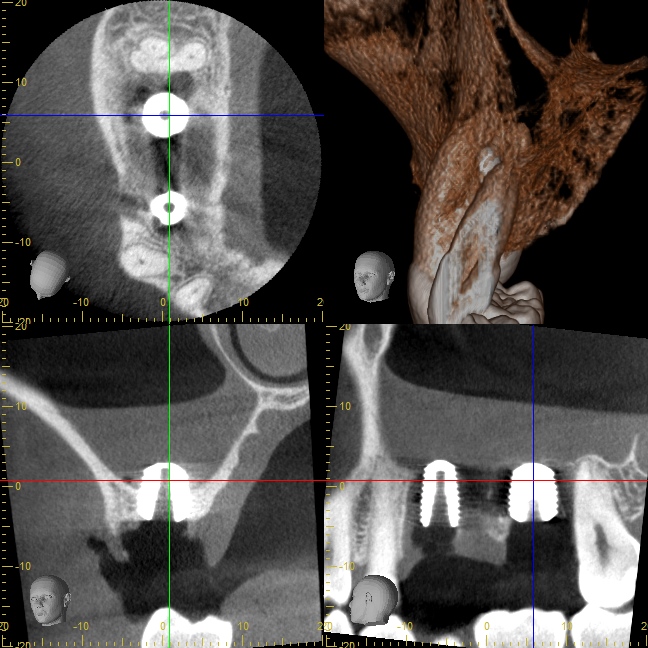

初診時のCT写真

残せない歯を他院さんで抜いたばかりのため、骨がとても少ない状態です。

こちらも顎骨が非常に薄く、上顎洞(副鼻腔)までの距離は3ミリくらいしかありません。

オペ後のCT写真

インプラント先端が少しだけ上顎洞(副鼻腔)に突き出てるように見えますが、問題はありません。

ご自分の骨で持ち上げられたスペースには血液がたまり、少しずつ骨に置換していきます。

治療後のCT写真

インプラント周囲に健全な骨が再生されています。

上顎洞粘膜をDensah® Burでリフトアップした部分にも緻密な骨が再生されました。